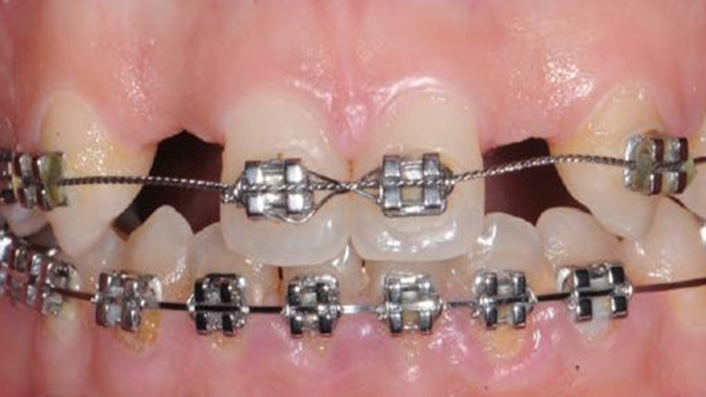

Socket Shield Technique, anterior esthetics, maxillary anterior, esthetic, esthetics, delayed implant placement, socket preservation, AnyRidge, Root Membrane Kit, Root Membrane Technique, Partial Extraction Therapy, PET, esthetic zone, fuse abutment, Dr. Yoshiharu Hayashi,#11,#21,#22

Anterior esthetics, MiNi, flap elevation, minimally invasive technique, soft tissue management, esthetic zone, Dr. Achraf Souayah, anterior aesthetics, aesthetic, aesthetics, esthetic, #12, #22